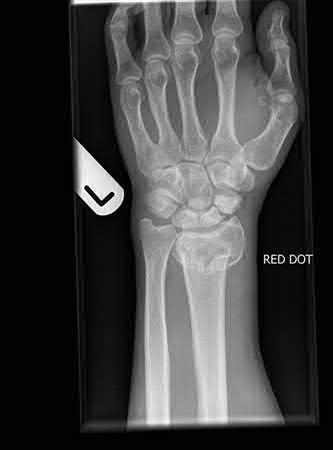

What is the most common type of malalignment after intramedullary nailing of distal 1/3 extra-articular tibia fractures using a infrapatellar approach when compared with plating?

The most common type of malalignment after intramedullary nailing of distal 1/3 extra-articular tibia fractures using an infrapatellar approach when compared with plating is valgus malalignment.

Fixation of distal one-third tibial shaft fractures can be successfully treated with either intramedullary nailing or plating. The literature describes advantages and disadvantages to both approaches, however intramedullary nailing has been shown to lead to increased rates of valgus malunion. Recent studies have shown that using a suprapatellar approach may decrease the incidence of valgus malalignement.

Vallier et al performed a randomized prospective study to compare plate and nail stabilization for distal tibia shaft fractures by assessing complications and secondary procedures. One-hundred and four patients were randomized to either reamed intramedullary nailing, or medial distal tibia plate fixation.

Primary angular malalignment was identified in 17 patients (16.3%). This included four patients treated with tibial plating (8.3%) and 13 patients treated with nails (23%, P = 0.02). Eight of these (7.7% of all patients) had malalignment between 6° and 10° of angulation. Valgus was the most common

angular deformity, accounting for 70% of angular deformity cases.

Avilucea et al. looked at the immediate postoperative alignment of distal tibia fractures (within 5 cm of the tibial plafond) treated with suprapatellar intramedullary nail (IMN) insertion compared with the infrapatellar technique. They found primary angular malalignment of ≥5 degrees occurred in 35 (26.1%) patients with infrapatellar IMN insertion and in 5 (3.8%) patients who underwent suprapatellar IMN insertion. They conclude suprapatellar IMN technique results in a significantly lower rate of malalignment compared with the infrapatellar IMN technique.